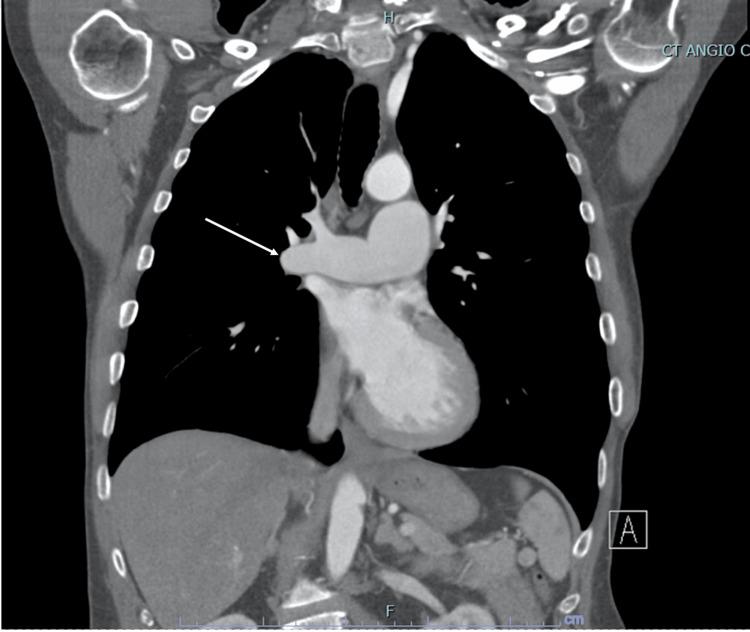

Infective endocarditis (IE) is a microbial infection affecting cardiac valves. IE most often affects the aortic valve and is commonly caused by community-acquired, penicillin-sensitive streptococcus that enters through the oral cavity. In this report, we present a case of a 66-year-old man with a medical history of congenital pulmonic stenosis status after pulmonic valve (PV) repair. The patient underwent a transesophageal echocardiogram showing a 1 cm × 0.7 cm mobile vegetation attached to the ventricular aspect of the right coronary aortic cusp and a 1.1 cm × 0.5 cm mobile vegetation attached to the arterial aspect of the PV cusp. In conclusion, concomitant right- and left-sided IE is an exceedingly rare condition. Due to its rarity and complexity of presentation, pulmonic valve endocarditis (PVE) requires a multidisciplinary approach to its perioperative management to prevent systemic complications.

感染性心内膜炎(IE)是一种影响心脏瓣膜的微生物感染。IE最常累及主动脉瓣,通常由经口腔进入的社区获得性、对青霉素敏感的链球菌引起。在本报告中,我们介绍了一例66岁男性患者,其有先天性肺动脉狭窄病史,曾接受肺动脉瓣(PV)修复术。患者接受经食管超声心动图检查,显示一个1 cm×0.7 cm的活动赘生物附着于右冠状动脉主动脉瓣叶的心室面,以及一个1.1 cm×0.5 cm的活动赘生物附着于PV瓣叶的动脉面。总之,双侧IE是一种极其罕见的情况。由于其罕见性和临床表现的复杂性,肺动脉瓣心内膜炎(PVE)需要多学科方法进行围手术期管理,以预防全身并发症。